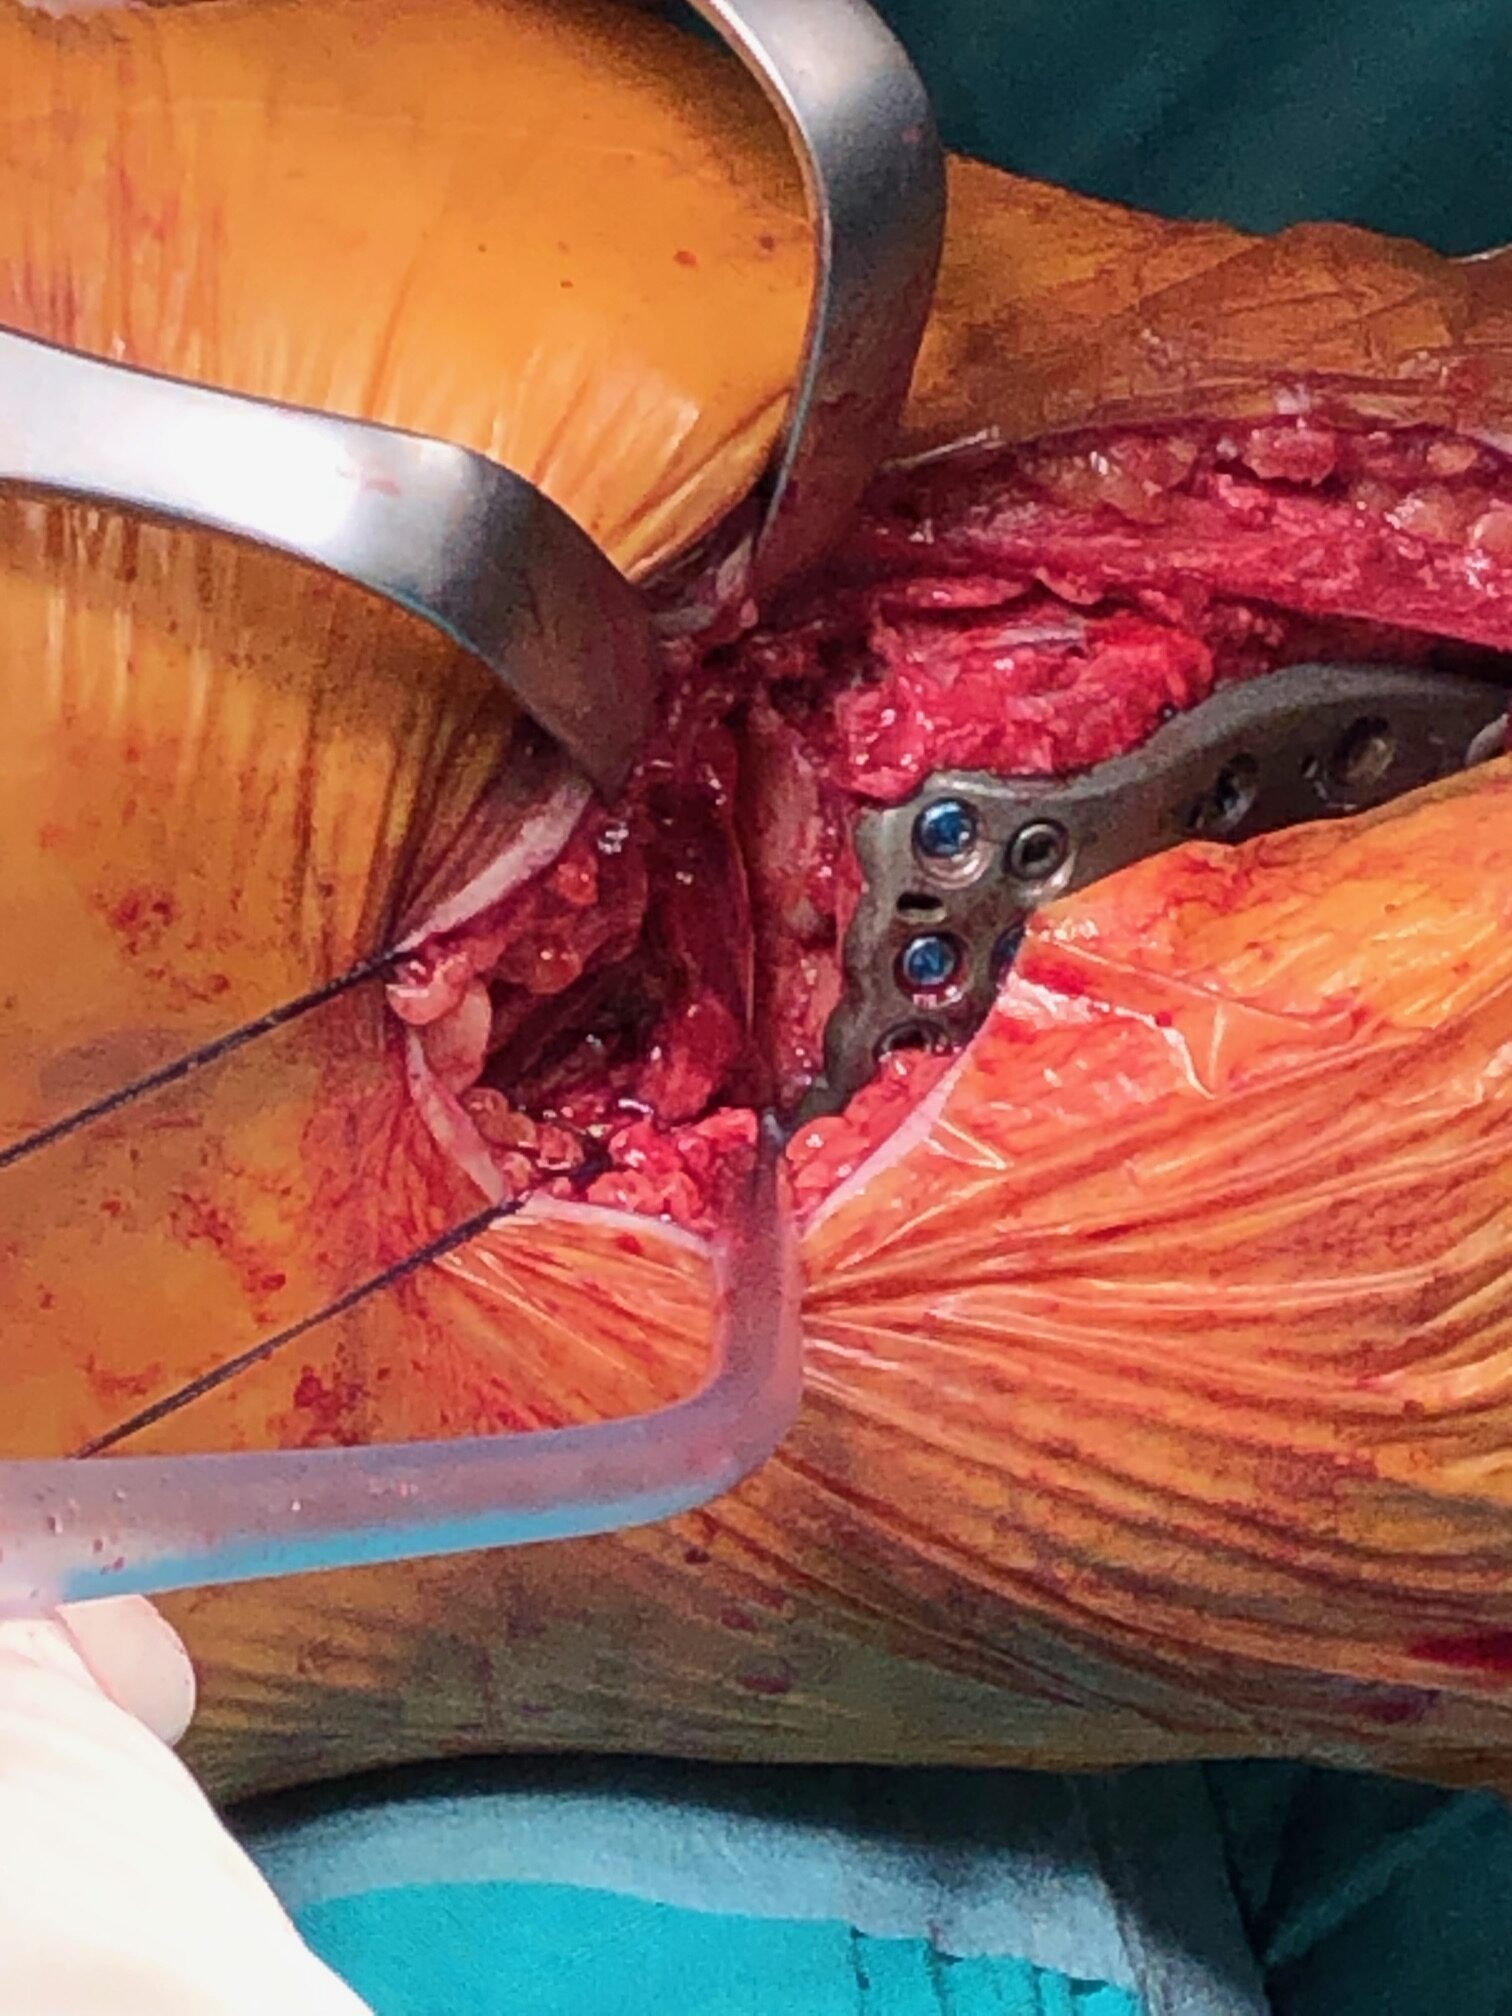

Σε κατάγματα του κνημιαίου plateau με μεγάλη συντριβή, με εμβύθιση της αρθρικής επιφανειας ή σε ασθενείς με αθλητική δραστηριότητα συστήνεται η χειρουργική αντιμετώπιση. Αυτή συνίσταται στην ανοικτή ανάταξη του κατάγματος και την εσωτερική οστεοσύνθεση του (τοποθέτηση πλάκας και βιδών), την τοποθέτηση εξωτερικής οστεοσύνθεσης ή στον συνδυασμό μεθόδων. Σε επιλεγμένα περιστατικά μπορεί να γίνει η ανάταξη του κατάγματος υπό αθροσκοπικό έλεγχο.